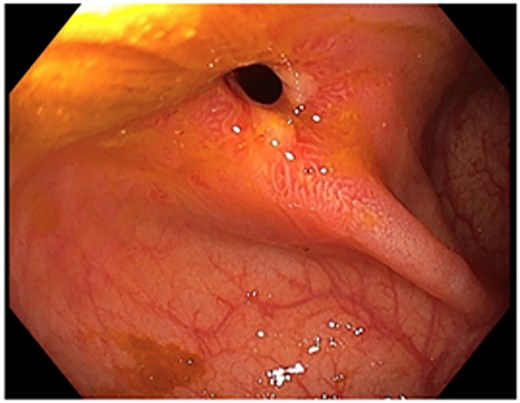

A 48-year-old lady with a background history of chronic migraines and family history of Crohn’s Disease presented to the emergency department with a three-day history of worsening abdominal pain and obstipation. She underwent a colonoscopy three days prior, which demonstrated shallow ulceration in the rectum and distal colon as well as a web-like stenosis in the ascending colon, 60 cm from the anal verge. The stenotic region was <5 mm in size and was unable to be traversed by the colonoscope, suspicious for a newly diagnosed stricturing Crohn’s disease (Fig. 1). She admitted to taking indomethacin suppositories 100 mg daily over the last two years for her migraines, as well as propranolol, triptan, ondansetron and sertraline. On examination her abdomen was soft, and tender in the right paraumbilical region without peritonism. Her haemoglobin was 94 g/L (115–165 g/L), C reactive protein (CRP) demonstrated a moderate inflammatory process at 40 mg/L (< 5 mg/L). Serum biochemistry and white cells were within normal limits. Computed tomography (CT) demonstrated a stricture in the ascending colon with an evolving proximal large bowel obstruction (Fig. 2). There was faecalisation in the terminal ileum suggestive of an acute on chronic obstruction. There was no suggestion of gastrointestinal perforation, or metastatic disease. The patient was made nil by mouth and prescribed intravenous hydrocortisone 100 milligrams four times a day by the gastroenterologist for suspected Crohn’s disease. However, the patient failed to progress after four days of hydrocortisone. A colonoscopic balloon dilatation was attempted with a 6 mm balloon, however the stricture appeared well-established, and the site began to bleed after the first attempt (Fig. 3). Subsequent attempts were abandoned due to the risk of bowel perforation. The distal end of the stricture was tattooed using spot ink. A colorectal surgeon became involved in her care who recommended a laparoscopic right hemicolectomy.

Colonoscopic picture of the diaphragm-like stricture in the ascending colon, 60 cm from the anal verge.